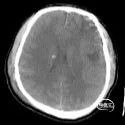

辅助检查:入院当天头部CT示:双侧额顶叶、左侧颞叶脑挫裂伤,最大截面约3.05×2.30cm,蛛网膜下腔出血。